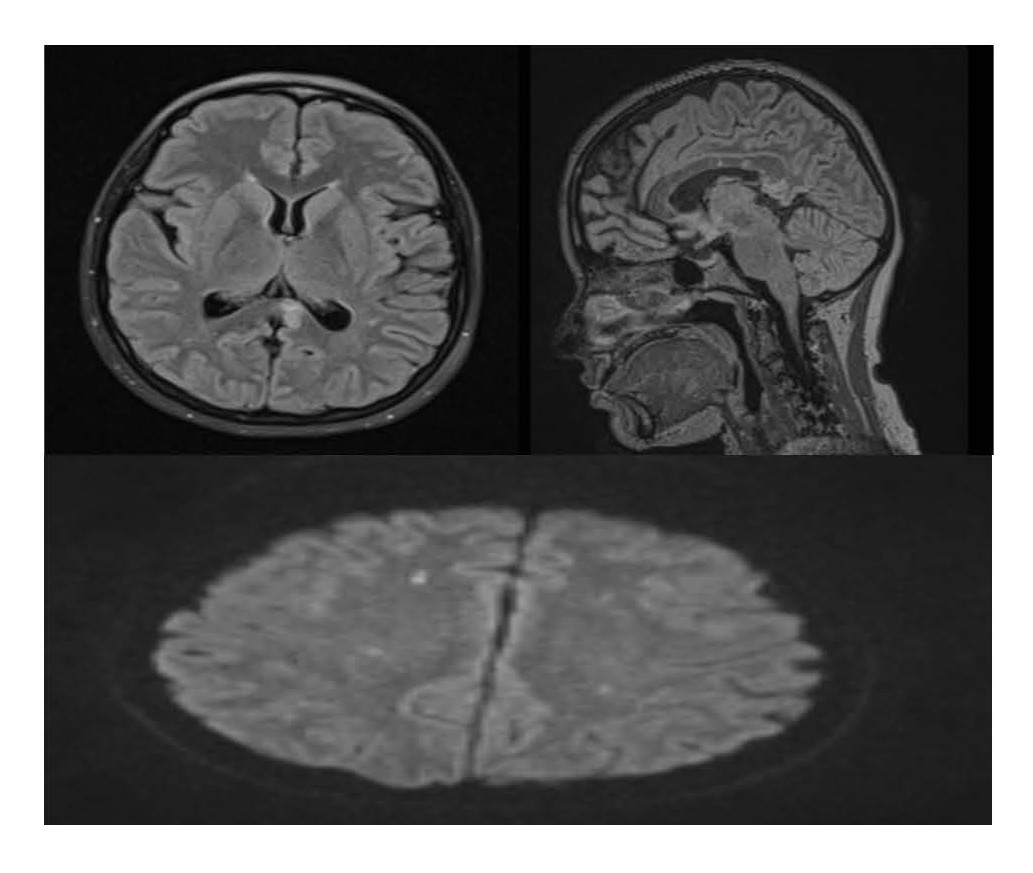

Figure 3. 21-Nov-2023 MRI: (1,2) Axial/Sagittal FLAIR/T2 shows regression in lesion size (indicating partial recovery), (3) also on DWI there are multiple tiny diffusion restrictions (microinfarcts).

Neurological Status shows marked improvement in cognitive function and resolution of disorientation. Her follow-up MRI showed regression of corpus callosal lesions. Audiological reassessment shows residual mild sensorineural hearing loss persisted despite treatment. Ophthalmological reassessment shows persistent BRAO with no further deterioration. Coagulation Monitoring and Warfarin therapy continued, with future reassessment planned based on disease activity.